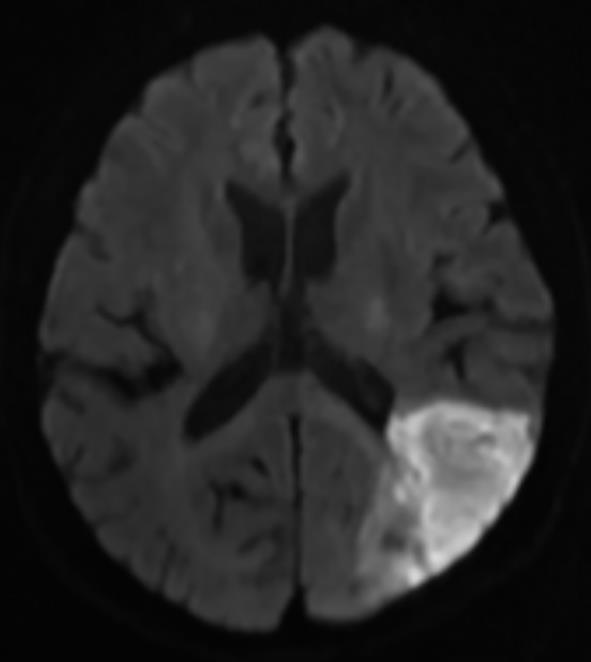

该文追踪1例低叶酸血症患者6年,观察患者体内血栓的动态演变过程。对该例患者进行了叶酸水平、同型半胱氨酸、维生素B12水平监测,同时监测患者的颈动脉超声、下肢动脉超声、头颅磁共振成像和磁共振血管成像,并获得患者的基因学检测结果。第1年,患者出现了左侧大脑中动脉皮质支闭塞(叶酸2.23 ng/mL)。第2年,患者出现了左下肢深静脉血栓(叶酸2.58 ng/mL)。第3年,患者出现左侧颈内动脉颅内段大部分闭塞(叶酸2.16 ng/mL)。第4年,患者出现右下肢深静脉血栓+左侧颈内动脉颅外段狭窄+右下肺静脉血栓形成(叶酸2.27 ng/mL),此时启动了补充叶酸治疗。第5年,患者未再新发血栓。采用DNA微阵列法检测发现,该例患者基因组中MTHFR基因677位为T/T纯合型(突变型)。第6年,患者死于肺炎。该类型突变的患者会出现低叶酸血症,导致快速侵袭性、全身动静脉多发性血栓,补充叶酸治疗可能有效。

A patient with hypofolatemia was followed up for 6 years to observe the dynamic evolution of thrombus. The levels of folic acid, homocysteine, and vitamin B12 were monitored, as well as carotid artery ultrasound, lower extremity arterial ultrasound, cranial MRI, and MRA, and genetic testing results were obtained. The patient experienced occlusion of the cortical branch of the left middle cerebral artery (folic acid 2.23 ng/mL) in the first year, deep vein thrombosis of the left lower extremity (folic acid 2.58 ng/mL) in the second year, and occlusion of most of the intracranial segment of the left internal carotid artery (folic acid 2.16 ng/mL) in the third year. In the fourth year, the patient experienced deep vein thrombosis of the right lower extremity, stenosis of the extracranial segment of the left internal carotid artery, and venous thrombosis of the right lower lung, with a folic acid level of 2.27 ng/mL, and folate supplementation was initiated at this time. New-onset thrombus was not observed in this patient in the fifth year. DNA microarray analysis showed T/T homozygous type (mutant type) at the 677 locus of the MTHFR gene. The patient died of pneumonia in the sixth year. Patients with such mutation may develop hypofolatemia, leading to rapidly aggressive multiple arteriovenous thrombosis throughout the body, and folate supplementation might be an effective treatment method.

图1 头颅MRI平扫Fig.1

图3 头颅MRI平扫和MRA图像Fig.3

图6 头颅MRI平扫和MRA图像Fig.6